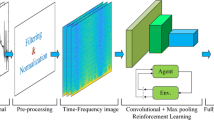

Individuals with Motor Neuron Disease were unable to move from one place to another because it gradually reduced all the voluntarily movement due to the degeneration of upper and lower motors neurons. The solution to this problem was to develop rehabilitating devices using biosignals. In this study, we have designed and developed electrooculogram-based wheelchair control using Cross Power Spectral Density. The convolution neural network to verify the performance and recognition accuracy of the wheelchair navigation in the indoor environment by using four trained users and four untrained users between the different age-groups and obtained the accuracy of 91.18% and 86.88% by using four fundamental tasks. From the indoor performance, the subject S4 from trained users outperforms all the trained subjects with an average classification accuracy of 93.51%. To verify the recognition accuracy, we conducted the online performance from the online performances subject S4 from trained subjects outperforms remaining trained subjects at the same time the subject S6 from untrained subjects outperforms all the untrained subjects. From the entire study, we analyzed that classification accuracy of subjects S4 was appreciated compared to other subjects. Through the research, we confirmed that the entire trained subject’s performance was maximum compared to the untrained subjects in all the circumstances.

Teng G, He Y, Zhao H, Liu D, Xiao J, Ramkumar S (2020) Design and development of human computer interface using electrooculogram with deep learning. Artif Intell Med 102:101765

Tang W, Wang A, Ramkumar S, RadhakrishnanNair RK (2020) Signal identification system for developing rehabilittive device using deep learning algorithms. Artif Intell Med 102:101755